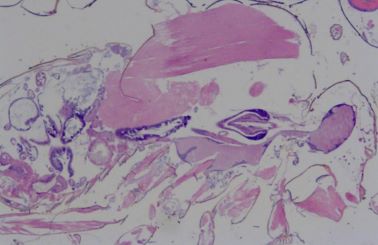

BRAF and KRAS Hotspot Analysis of TSA and TA Precursor Lesions in FAP  Patients

Alexander Wilentz, Pine Crest School

This study investigated specific hotspot mutations in the KRAS and BRAF oncogenes in colorectal cancer precursor lesions TSA and TA in FAP patients.